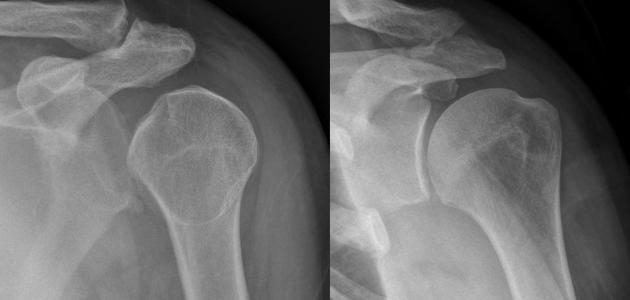

يحدث خلع الكتف نتيجة خروج مفصل اليد العُلوي عن تجويف الكتف؛ نتيجة السقوط عليه، أو تعرُّضه للإصابة، ويُرافق خلع الكتف ظهور العديد من الأعراض، وفيما يأتي بعض منها:[١]

- تشوُّه الكتف؛ أي ظهور بروز في الجزء الأماميّ، أو الخلفيّ من الكتف.